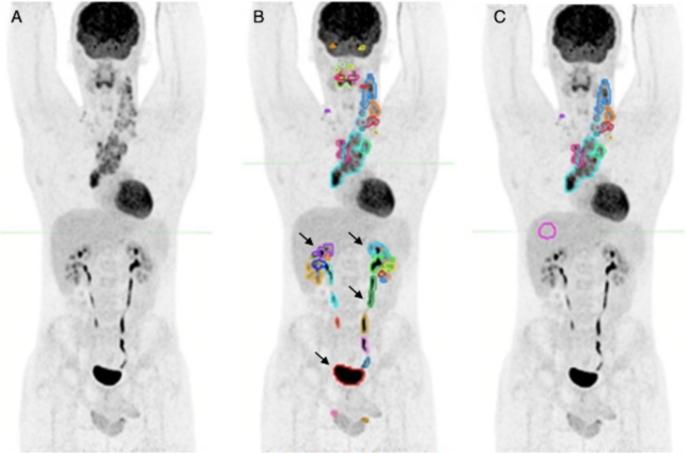

In a previous preliminary study, radiomic features from the largest and the hottest lesion in baseline F-FDG PET/CT (bPET/CT) of classical Hodgkin's Lymphoma (cHL) predicted early response-to-treatment and prognosis. Aim of this large retrospectively-validated study is to evaluate the predictive role of two-lesions radiomics in comparison with other clinical and conventional PET/CT models. cHL patients with bPET/CT between 2010 and 2020 were retrospectively included and randomized into training-validation sets. Target lesions were: Lesion_A, with largest axial diameter (D); Lesion_B, with highest SUV. Total-metabolic-tumor-volume (TMTV) was calculated and 212 radiomic features were extracted. PET/CT features were harmonized using ComBat across two scanners. Outcomes were progression-free-survival (PFS) and Deauville Score at interim PET/CT (DS). For each outcome, three predictive models and their combinations were trained and validated: - radiomic model "R"; - conventional PET/CT model "P"; - clinical model "C". 197 patients were included (training = 118; validation = 79): 38/197 (19%) patients had adverse events and 42/193 (22%) had DS ≥ 4. In the training phase, only one radiomic feature was selected for PFS prediction in model "R" (Lesion_B F_cm.corr, C-index 66.9%). Best "C" model combined stage and IPS (C-index 74.8%), while optimal "P" model combined TMTV and D (C-index 63.3%). After internal validation, "C", "C + R", "R + P" and "C + R + P" significantly predicted PFS. The best validated model was "C + R" (C-index 66.3%). No model was validated for DS prediction. In this large retrospectively-validated study, a combination of baseline F-FDG PET/CT two-lesions radiomics and other conventional models showed an added prognostic power in patients with cHL. As single models, conventional clinical parameters maintain their prognostic power, while radiomics or conventional PET/CT alone seem to be sub-optimal to predict survival.

在之前的一项初步研究中,经典型霍奇金淋巴瘤(cHL)基线F-FDG PET/CT(bPET/CT)中最大且最热点状病变的放射组学特征可预测早期治疗反应和预后。这项大型回顾性验证研究的目的是评估双病变放射组学与其他临床及传统PET/CT模型相比的预测作用。回顾性纳入了2010年至2020年间进行bPET/CT检查的cHL患者,并随机分为训练-验证集。目标病变为:病变A,具有最大轴向直径(D);病变B,具有最高SUV。计算总代谢肿瘤体积(TMTV)并提取212个放射组学特征。使用ComBat对两台扫描仪的PET/CT特征进行标准化。观察指标为无进展生存期(PFS)和中期PET/CT时的迪沃利评分(DS)。对于每个观察指标,训练并验证了三种预测模型及其组合:- 放射组学模型“R”;- 传统PET/CT模型“P”;- 临床模型“C”。纳入了197例患者(训练组 = 118例;验证组 = 79例):197例患者中有38例(19%)发生不良事件,193例患者中有42例(22%)DS≥4。在训练阶段,模型“R”中仅选择了一个放射组学特征用于PFS预测(病变B F_cm.corr,C指数66.9%)。最佳“C”模型结合了分期和国际预后评分(IPS)(C指数74.8%),而最佳“P ”模型结合了TMTV和D(C指数63.3%)。经过内部验证,“C”、“C + R”、“R + P”和“C + R + P”显著预测了PFS。验证效果最佳的模型是“C + R”(C指数66.3%)。没有模型被验证可用于DS预测。在这项大型回顾性验证研究中,基线F-FDG PET/CT双病变放射组学与其他传统模型的组合在cHL患者中显示出额外的预后预测能力。作为单一模型,传统临床参数保持其预后预测能力,而单独的放射组学或传统PET/CT在预测生存方面似乎并不理想。